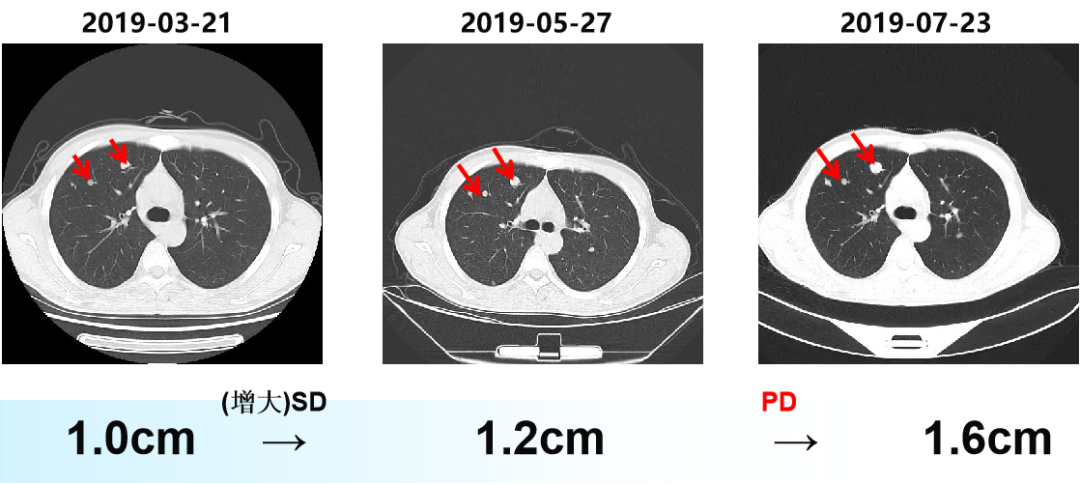

二 病例分享 专家简介 01 基本情况 刘某某,男性,28岁。 主诉:大便次数增多2月。 首诊时间:2018-07-03,北京大学人民医院。 既往史:右踝关节骨折术;痔疮病史。 个人史:无特殊。 家族史:其父为小细胞肺癌患者。 入院查体:ECOG 1分,无明显阳性体征。 02 初诊病史 肿瘤标志物:CEA 19.45 ng/ml。 肠镜及病理:直肠(距肛门约8cm处),直肠腺癌。 胸腹盆增强CT:1.双肺多发结节,考虑转移瘤可能性大;2.肝S6段异常密度灶;3.下段直肠癌可能性大。 盆腔增强MRI:(中位)直肠癌、T(3b)、N(2b)、癌结节(0)、CRM(阳性)、EMVI(阴性)、非区域淋巴结(阴性)。 上腹部增强MRI:肝S6段小结节,不典型血管瘤可能大。 初步诊断: 1.直肠癌(cT3N2bM1aIVA期 )肺转移; 2.痔疮; 3.右踝关节骨折术后; 4.肝血管瘤。 03 治疗方案 外院:XELOX。 我院首诊:2018-07-18。 免疫组化:MLH1(+),PMS2(+),MSH2(+),MSH6(+)。 2018-07-25至2018-09-26 XELOX *2+局部放疗*25f,PD。 基因检测(2018-10-23):KRAS、NRAS、BRAF基因均未见突变。 二线治疗:2018-10-18至2019-03-01 贝伐珠单抗+FOLFIRI*9 (SD→PD)。 疗效评估 三线治疗:2019-03-28至2019-07-23 西妥昔单抗+伊立替康+雷替曲塞*6(SD→PD)。 疗效评估 2019-07-25 瑞戈非尼 80mg po。 2019-09-26 复查:SD,瑞戈非尼 120mg po。 2019-11-21 复查:PD,瑞戈非尼 160mg po。 疗效评估 2019-12-19 至2020-09-24 信迪利单抗 200mg q3w +瑞戈非尼80mg po d1-d21 q4w。 2020年 ASCO 更新的瑞戈非尼+纳武利尤单抗(regorafenib+nivolumab)在晚期结直肠癌或胃癌患者中的Ib期临床试验(REGONIVO, EPOC1603)。 疗效评估 2020-09-26 盆腔增强MRI:直肠癌治疗后复查,与2020-05-10 MRI比较:直肠壁增厚程度较前似进展;直肠下段偏左侧新发不规则异常信号,考虑瘘管/脓肿形成。 考虑直肠下段脓肿,行抗感染治疗。 并于 2020-10-14 在气管插管全身麻醉下行腹腔镜下乙状结肠造口术。 2020-11-06 至2021-02-05 信迪利单抗200mg q3w+呋喹替尼3mg d1-21 q4w。 双肺多发转移瘤,对比 2020-11-04 CT较前增大、部分空洞形成。 TAS-102:新型口服细胞毒性药物 2021-V1版NCCN指南和2021 CSCO指南推荐更新:TAS-102±贝伐珠单抗(Bev)作为mCRC三线标准治疗。 2021-02-05 至今 TAS-102 60mg bid d1-5,d8-12,q4w 联合信迪利单抗200mg q3w。 不良反应 西妥昔单抗:皮疹; 瑞戈非尼:手足综合征; PD-1抑制剂:免疫性甲状腺炎; TAS-102:骨髓抑制(中性粒细胞IV度下降、贫血)。 04 诊疗小结